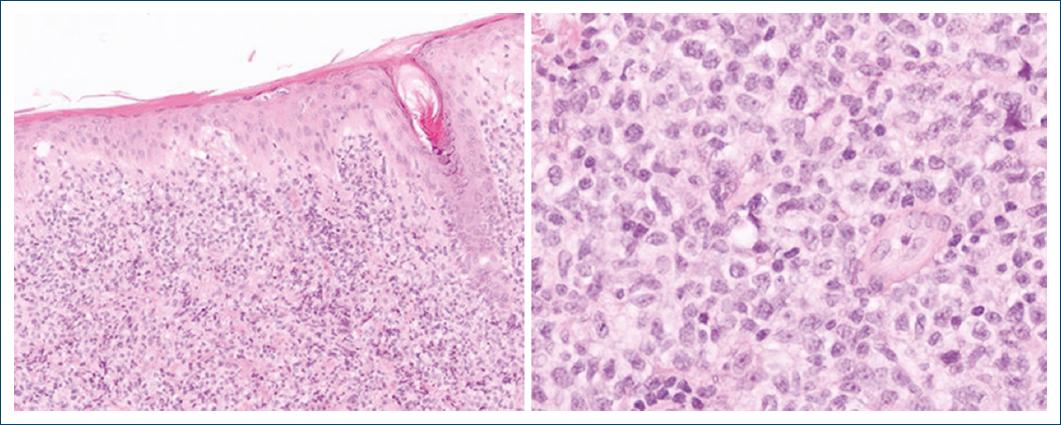

A 60-year-old patient, with a history of ankylosing spondylitis and autoimmune hemolytic anemia, under treatment with infliximab and low-dose prednisone for the past 9 years, was referred to the Hematology Department of our Hospital, for a suspected cutaneous lymphoma. On clinical observation, he presented with a 7 cm ulcerated, well-demarcated lesion on his left lower back and in the left scapular region with a 20 cm erythematous, and scaly patch with two infiltrated 4 cm plaques within it (Fig. 1). On palpation, there were no detectable lymphadenopathies or hepato-splenomegaly. The lesions had a 6-month evolution gradually transitioning from patches to plaques and tumours. A skin biopsy of the tumor phase (and later from the plaque phase), performed in the hospital of origin, was reviewed in our pathology department for a histopathological diagnosis. We observed a diffuse infiltration of the superficial and deep dermis by atypical, intermediate-size lymphocytes, with dispersed chromatin (Fig. 2). The neoplastic lymphocytes, evaluated in paraffin-embedded tissue, expressed CD2, CD3, CD56, TIA-1, Granzyme B, and TCRδ and negativity for CD4, CD5, CD7, CD8, CD20, CD30, BCL6, CD278, TCRβ, and PD-1 (Fig. 3). In situ hybridization analysis with EBER revealed nuclear positivity in all neoplastic cells. There was no evidence of epidermotropism, vasculotropism, or necrosis.

Figure 2 Infiltration of the dermis by atypical, intermediate size lymphocytes, with dispersed chromatin.